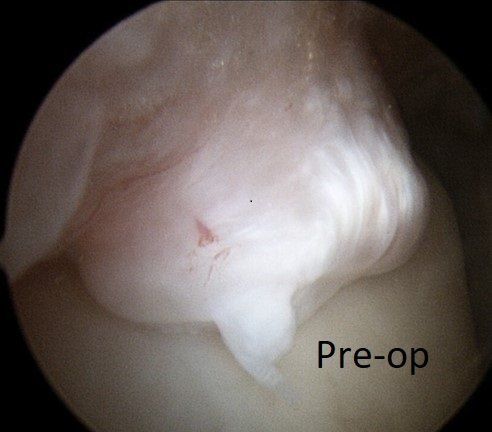

When symptoms persist, ankle arthroscopy is used to "clean-out" the ankle. Occasionally, the ankle needs to be opened to access deep scar tissue or very large spurs and bone fragments.

This procedure removes:

- scar tissue and inflammation (synovitis)

- bone spurs (see images below)

- loose bone and cartilage fragments.